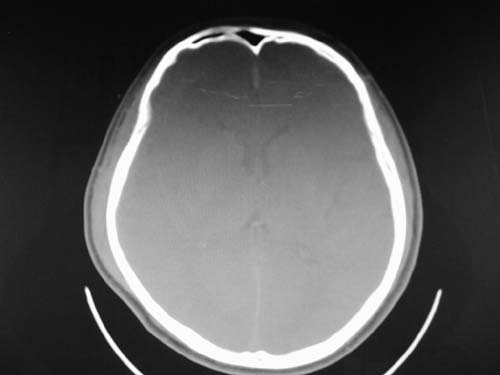

脑中线内血肿,是硬膜下的吗?

脑中线内血肿——硬膜下血肿。

脑中线内血肿——硬膜下血肿。我们一般认为中线即可是硬膜下,也可是蛛网膜下腔的。边缘锐利,张力高的考虑硬膜下的,边缘模糊的,考虑下腔的。如果有老师有肯定的答案,麻烦下给我发个短信

硬膜下血肿,有颅骨骨折

支持镰旁硬膜下血肿,颅骨骨折,头皮损伤.

这个病人年龄不小吧,右侧脑沟不清,中线结构稍有左移,右侧额颞顶及右镰旁硬膜下血肿,另有蛛血,骨折。

外伤后引起的颅骨骨折、硬膜下血肿、皮下血肿,颅骨骨折引起的矢状窦破裂,形成大脑纵裂内血肿。